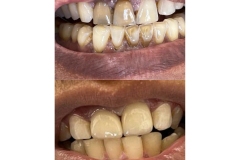

Tooth restorations are the various ways your dentist can replace missing teeth or repair missing parts of the tooth structure. Tooth structure can be missing due to decay, deterioration of a previously placed restoration, or fracture of a tooth.

Both crowns and most bridges are fixed prosthetic devices. Unlike removable devices such as dentures, which you can take out and clean daily, crowns and bridges are cemented onto existing teeth or implants, and can only be removed by a dentist.